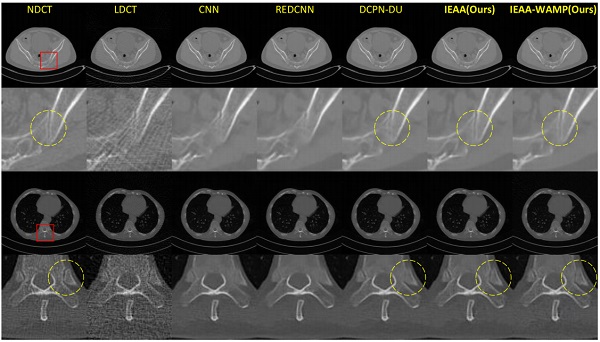

当前,随着CT成像技术在临床诊断尤其是常规检查中的普及,CT检查的辐射剂量问题已经引起了人们越来越多的关注。大量的临床研究表明,超过正常范围的CT辐射剂量易诱发人体新陈代谢异常乃至癌症等疾病。然而,在目前的CT设备中,单方面减少CT扫描中的剂量将增加重建图像的噪声和伪影,降低CT重建的图像质量(图1),从而影响临床医生对病变组织的确诊率。低剂量CT重建技术旨在通过自适应的图像重建和图像处理算法来提高低剂量扫描条件下的CT图像质量,使得低剂量CT重建图像质量达到或接近正常剂量条件下的图像质量,从而实现在低辐射剂量情况下满足临床CT诊断要求。

考虑到CT影像的解剖部位先验信息,研究团队构建基于自适应解剖部位的深度学习算法,将解剖部位信息融合到低剂量CT影像重建过程当中(图2)。相较于不考虑解剖部位的一般深度学习方法,提出算法可以有效提高图像重建的峰值信息噪比(PSNR)和结构相似度(SSIM)等指标,可视化结果更佳(图3)。相关研究成果先后发表在IEEE Journal of Biomedical and Health Informaticsdoi: 10.1109/JBHI.2021.3061758)和Neurocomputing 期刊上(Vol. 428, pp. 104-115, 2021)。

为了去除低剂量CT图像噪声和伪影,研究团队提出将循环一致性的生成对抗网络应用到低剂量CT重建领域,并结合十字交叉(Criss-cross)的self-attention技术提取更高效的特征信息,进而生成分辨率更佳的高质量CT图像(图5)。实验结果表明提出方法具有良好的低剂量CT伪影去除效果。相关研究成果发表在IEEE Transactions on Computational Imaging 期刊上(Vol. 6, pp. 1203-1218, 2020)。

考虑到剂量的不同导致低剂量CT重建任务挑战难度也不同,剂量越低往往导致低剂量CT重建越具有挑战性。研究团队提出自适应剂量估计的深度学习低剂量CT重建模型,该模型流程主要分为两个步骤:第一,根据输入的低剂量CT图像估计出其相应的剂量等级;第二,结合估计出的剂量等级知识融合到后续的低剂量CT重建过程当中(图6)。实验表明提出的自适应剂量估计模型在噪声和伪影去除方面相较于其他模型更具有优势。相关研究成果发表在Physics in Medicine and Biology 期刊上(Vol. 66, No. 1: 015005, 2021)。